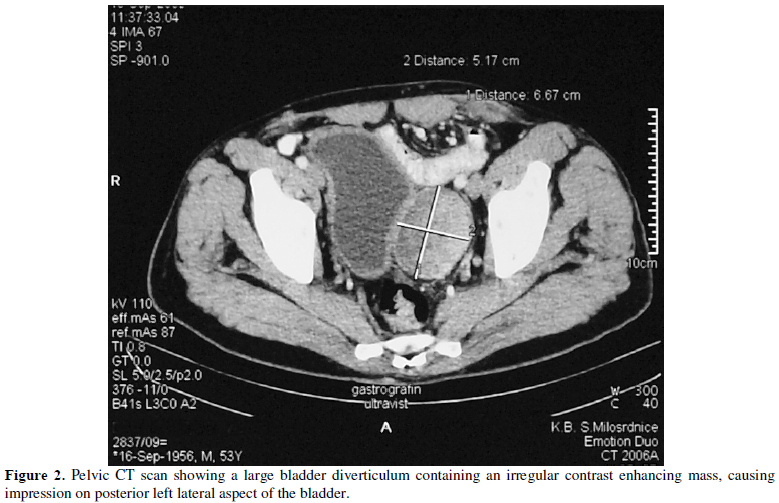

of the urinary bladder (Figure 1) A CT scan of the pelvis (Figure

2) showed an irregular contrast enhancing tumor mass filling bladder

diverticulum and measuring 6 cm in diameter. The patient underwent transvesical